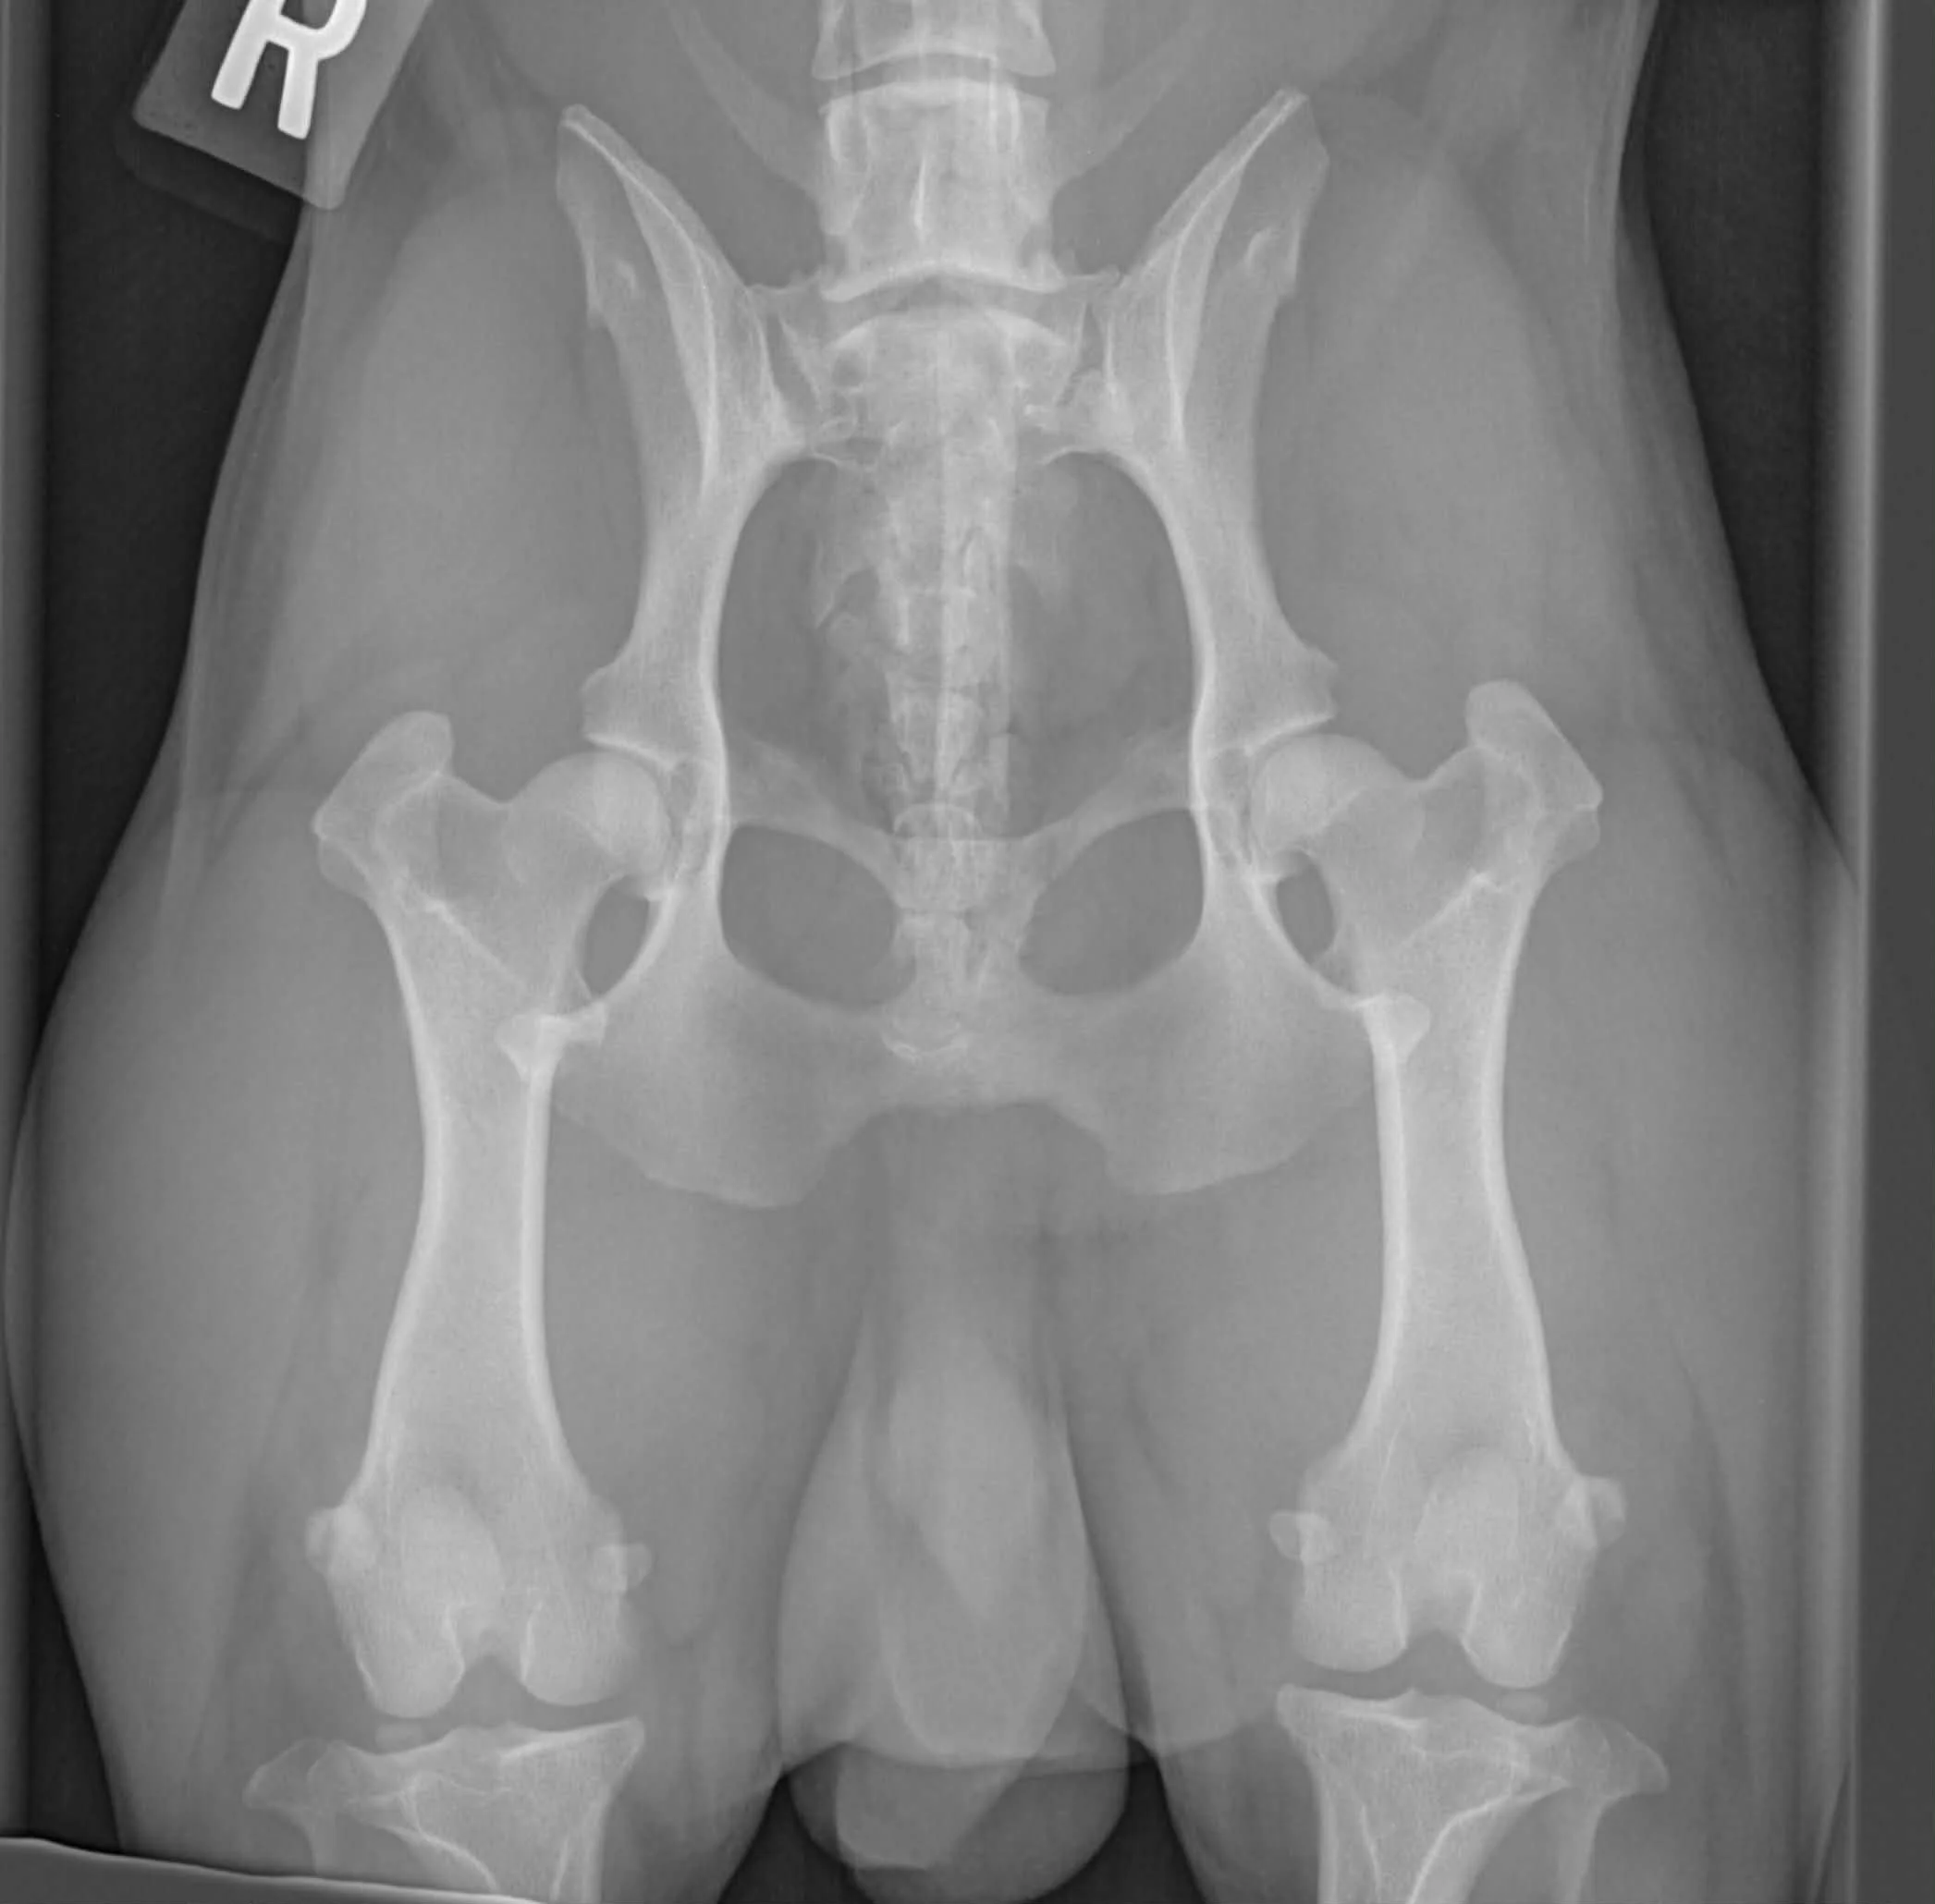

Dysplasie des Hanches

Anomalie du développement de la hanche qui mène éventuellement à la dégénérescence de celle-ci. La hanche normale se présente comme une boule à l’intérieur d'une cavité. Lors de la dysplasie de la hanche, l'articulation est souvent peu profonde et la tête fémorale petite et déformée.

La dysplasie de la hanche est une maladie complexe dont les causes ne sont pas totalement éclaircies bien que différents facteurs de risque aient été identifiés : Hérédité, croissance, alimentation, activités…

Les radiographies officielles peuvent être faites à partir de 24 mois et l’évaluation de celles-ci doit être effectuée par des spécialistes tels que OFA ou Pennhip.